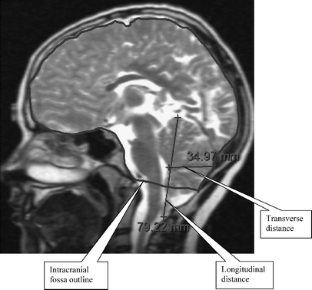

A midsagittal brain MRI slice was selected from each of 68 participants with CII (mean age 13 years). Control participants were 28 typically developing children (mean age 14.1 years). Midsagittal surface areas occupied by the intracranial fossa, posterior fossa, vermis, and its lobules were measured.

Fig. 1